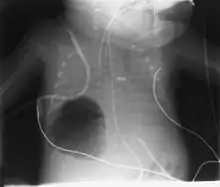

O diagnóstico pode ser feito por radiografia de tórax; a lesão aparece como uma pequena área redonda cheia de ar. A tomografia computadorizada pode fornecer uma compreensão mais detalhada da lesão.[1] Diagnósticos diferenciais – outras condições que podem causar sintomas semelhantes aos da pneumatocele incluem câncer de pulmão, tuberculose[7] e abscesso pulmonar[1] no contexto da síndrome de Hiper IgE (também conhecida como síndrome de Jó) e como uma complicação da pneumonite por COVID-19.[8]